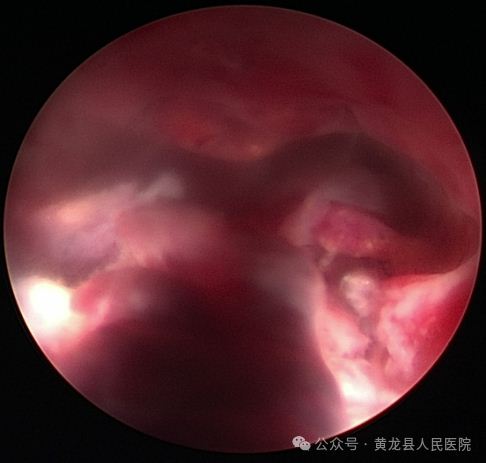

经宫腔镜子宫黏膜下肌瘤切除术(冷刀刨削)。

患者女,50岁,因不规则阴道出血11天来我院妇科就诊,彩超提示子宫后壁可见2.4cm×1.5cm低回声,考虑黏膜下肌瘤。经过严密术前评估,征求患者及家属意见后,决定实施经宫腔镜子宫黏膜下肌瘤切除术(冷刀刨削)。手术在硬腰联合麻醉下进行,宫腔镜直视肌瘤位置,见瘤体根蒂位于子宫后壁大小约3.5×2.5cm。张海红副主任医师用冷刀刨削缩小肌瘤体积,将子宫肌瘤全部取出,手术顺利,术后患者安返病房。由于宫腔镜手术没有体表手术伤口,术后6小时即可下床活动,并进食,术后2天顺利出院。术后病理检查:子宫黏膜下平滑肌瘤,与术前诊断一致。

术前宫腔术后宫腔